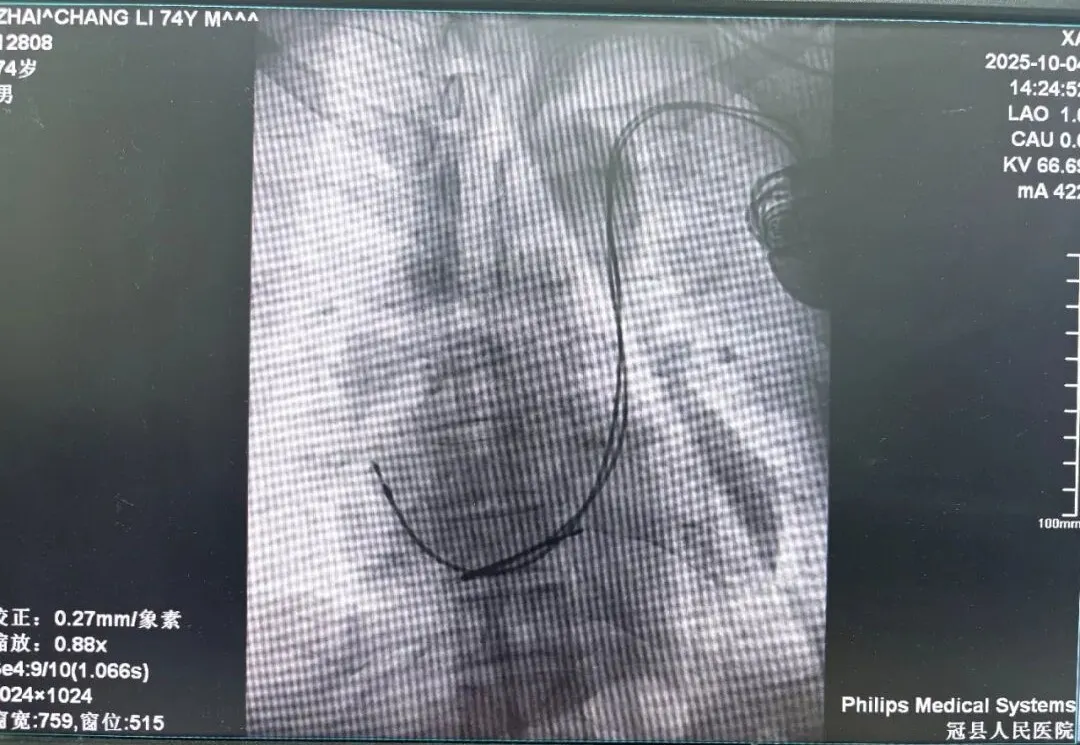

面对这一危急情况,心内一科团队迅速制定治疗方案,并依托与医生集团的常态化协作机制,特邀北京安贞医院戴文龙主任前来指导并主刀手术。术中,团队发现患者存在“永存左上腔静脉”这一罕见的血管解剖变异,显著增加了手术难度与风险。戴文龙主任凭借丰富的起搏器植入经验,沉着应对,精细操作,仅用一小时就成功将起搏电极放置到位,并顺利植入起搏器。术中测试显示,起搏信号清晰、感知良好、各项参数均达理想标准,为患者建立起一道坚实的“生命防线”。